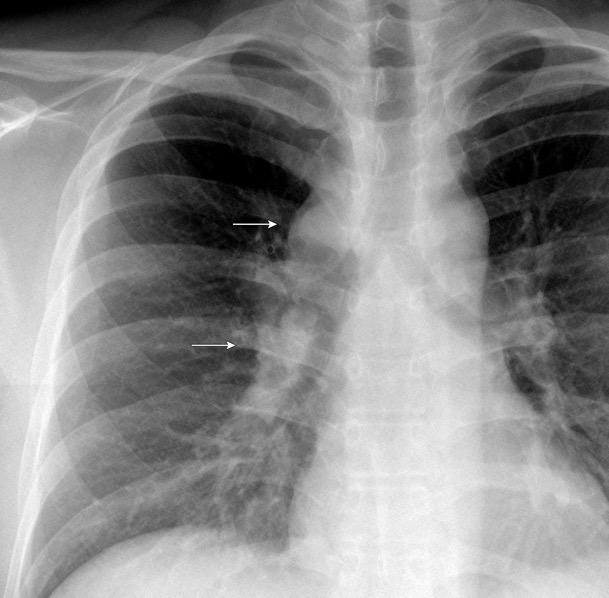

Triada de Garland

Ganglios paratraqueales derechos e hiliares bilaterales

95% de pacientes tienen ganglios hiliares bilaterales aislados o con afectación mediastínica (espec. paratraqueal derecho).

Criado E et al. Pulmonary sarcoidosis: typical and atypical manifestations at high-resolution CT with pathologic correlation. Radiographics. 2010